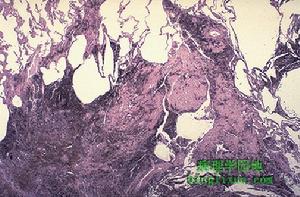

(3)腹腔動脈和腸系膜上動脈造影及間接門靜脈造影:選擇性動脈造影也可明確診斷,此時常可顯示狹窄的5.99Tc肝掃描99Tc肝掃描診斷BCS的特徵表現是肝臟增大,形態失常。示蹤劑聚集於充血肥大的肝尾葉,呈“中央濃集”現象,肝右葉示蹤劑呈稀疏狀分布或明顯減少。部分病人,脾臟中度或重度顯影和增大。內鏡檢查胃鏡僅可檢出食管-胃底靜脈曲張,對BCS的診斷幫助不大。腹腔鏡檢查對BCS的診斷具有重要意義,鏡下肝臟明顯腫大,表面光滑,外觀呈紫色。直視下活檢可以明確診斷。肝活檢BCS時肝臟組織學均可呈現特徵性變化,只要臨床症狀排除心源性因素,肝活檢一般都可作出明確診斷。然而,該檢查不能確定阻塞的性質、部位和範圍,不能代替血管造影檢查。有嚴重出血傾向和大量腹水時,行肝穿刺有一定危險,故不宜作為手術前常規檢查項目。